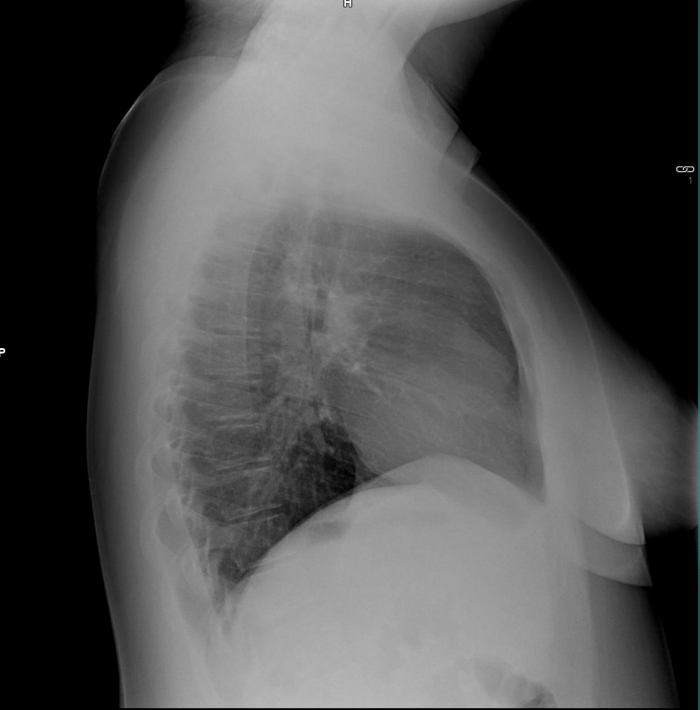

Se comparan radiografías de 3 años antes con las actuales:

3 años antes:

(Rx PA y lateral de tórax)

Ahora: